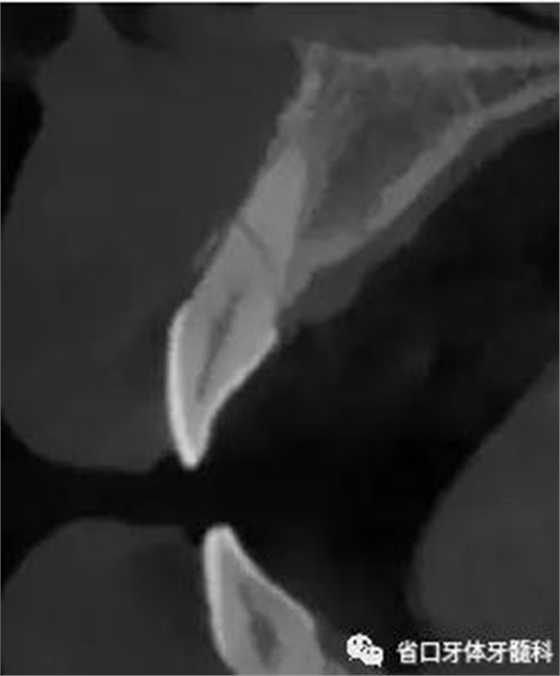

CBCT:11、21頸部以下均見一完全性折裂線,兩牙折裂線均位于頜骨內(nèi)且斷端移位不明顯,相應(yīng)唇側(cè)骨板亦見斷裂且輕度移位。

圖4:21術(shù)前